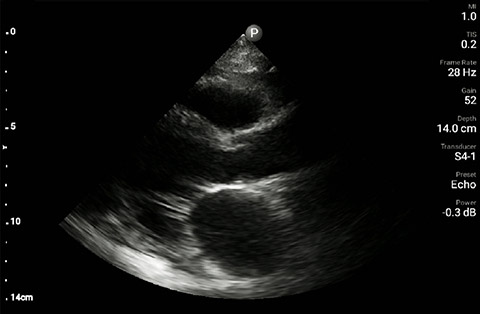

The patient had reduced LV systolic function without new or severe valvular pathology, a dilated, non-collapsing IVC, and diffuse B lines (left greater than right) on lung ultrasound imaging.

Parasternal long-axis

In the interim, while awaiting laboratory results and chest X-ray imaging, POCUS with a three-point exam (F-TTE, IVC collapsibility, and lung ultrasound) was used for bedside evaluation of the etiology of the patient’s dyspnea. Within minutes, and with the additive information from the combined cardiac, subcostal IVC, and lung ultrasound imaging, the patient was diagnosed with acute on chronic congestive heart failure and flash pulmonary edema as the cause of his respiratory distress and hypoxia.